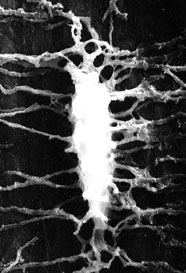

59. Lacune osteocitarie al microscopio ottico.

I vuoti (in nero) evidenziano sia le lacune sia la rete canalicolare pervia.Sezione di femore non decalcificata e non inclusa (Homo).